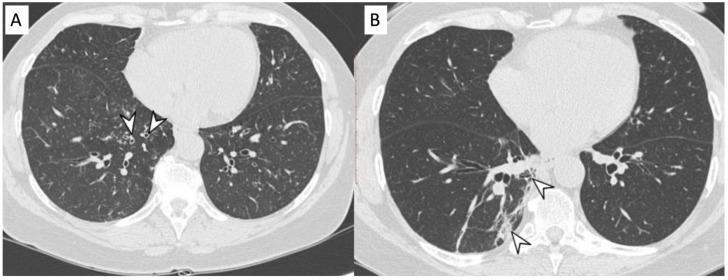

Vasculitides represent a heterogeneous group of immune-mediated disorders, characterized by a systemic inflammatory destructive process of the blood vessels resulting either in ischemia or hemorrhage. The organ involved and vessel size influence the pattern of presentation of the pathology. The lung is commonly involved in systemic vasculitides, with heterogeneous clinical, radiological, and histopathological presentations. Primary vasculitides most commonly associated with lung parenchymal involvement include small-vessel antineutrophil cytoplasmic autoantibody (ANCA)-associated vasculitides, such as granulomatosis with polyangiitis (GPA), eosinophilic granulomatosis with polyangiitis (EGPA), and microscopic polyangiitis (MPA). Several studies have reported cases of interstitial lung diseases (ILDs) associated with systemic vasculitis, particularly those positive for ANCA associated vasculitis/vasculitidis: AAV. We have selected from our case series different radiological features of pulmonary vasculitis (i.e., solitary or multiple nodules, cavitary lesions, nodules with centrilobular or peribronchial distribution, airspace consolidations, "crazy paving" appearance, interstitial disease), including cases with interstitial lung alterations. Therefore, the aim of this review is to describe the typical clinical manifestations of vasculitides and their main radiologic features (especially AAV).

血管炎是一组异质性的免疫介导性疾病,其特征是血管的系统性炎症性破坏过程,可导致缺血或出血。受累器官和血管大小会影响病理表现形式。肺部在系统性血管炎中常受累,临床表现、影像学表现和组织病理学表现各异。最常与肺实质受累相关的原发性血管炎包括小血管抗中性粒细胞胞浆自身抗体(ANCA)相关血管炎,如肉芽肿性多血管炎(GPA)、嗜酸性肉芽肿性多血管炎(EGPA)和显微镜下多血管炎(MPA)。多项研究报告了与系统性血管炎相关的间质性肺疾病(ILD)病例,尤其是那些ANCA相关血管炎/血管炎阳性的病例:AAV。我们从病例系列中选取了肺血管炎的不同放射学特征(即孤立或多发结节、空洞性病变、具有小叶中心或支气管周围分布的结节、气腔实变、“铺路石样”表现、间质性疾病),包括伴有间质性肺改变的病例。因此,本综述的目的是描述血管炎的典型临床表现及其主要放射学特征(尤其是AAV)。